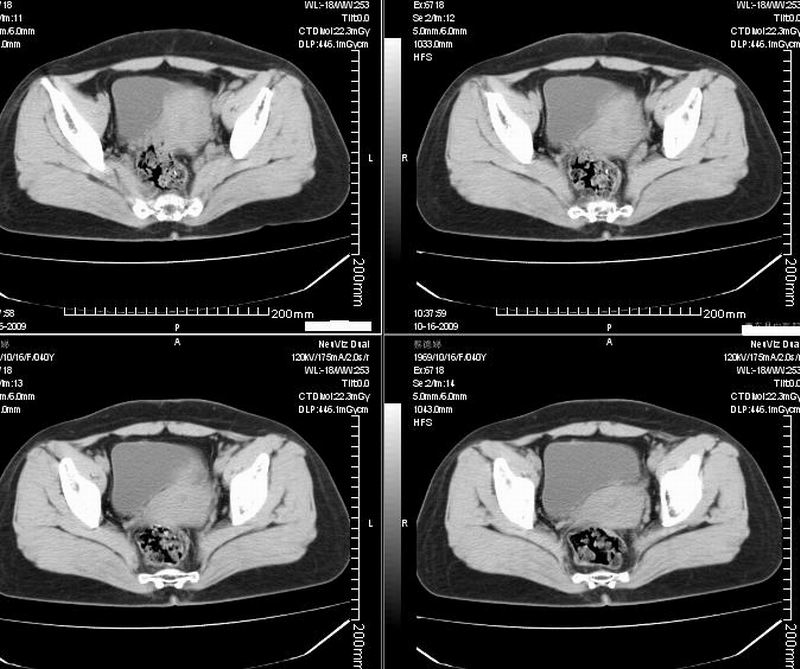

女:40y:下腹隐痛1周+,无其它不适,这个子宫会太一点吗?有临床意义吗?

宫腔内有积液,考虑炎症可能

子宫偏左,略显增大,期内可见低密度改变,考虑宫腔积液可能。

子宫偏左,略显增大,期内可见低密度改变,考虑宫腔积液可能。 不能除外肌瘤可能。

子宫体积稍增大,其内见低密度影。考虑宫腔积液可能。

子宫不规则的增大 宫腔内积液 有多种考虑

1 子宫肌瘤

2 子宫腺肌症

3 子宫内膜炎

4 月经期 (宫腔内积血)